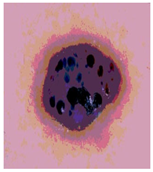

![]() | ![]() | ![]() | ![]() |

| Img1 | --- Pixel Intensity (0–255) ---> | ||

| Img2 | --- Pixel Intensity (0–255) ---> | ||

| Img3 | --- Pixel Intensity (0–255) ---> | ||

| Img4 | --- Pixel Intensity (0–255) ---> | ||

| Img5 | --- Pixel Intensity (0–255) ---> | ||

| Img6 | --- Pixel Intensity (0–255) ---> | ||

| Img7 | --- Pixel Intensity (0–255) ---> | ||

| Img8 | --- Pixel Intensity (0–255) ---> | ||

| Img9 | --- Pixel Intensity (0–255) ---> | ||

| Img10 | --- Pixel Intensity (0–255) ---> | ||